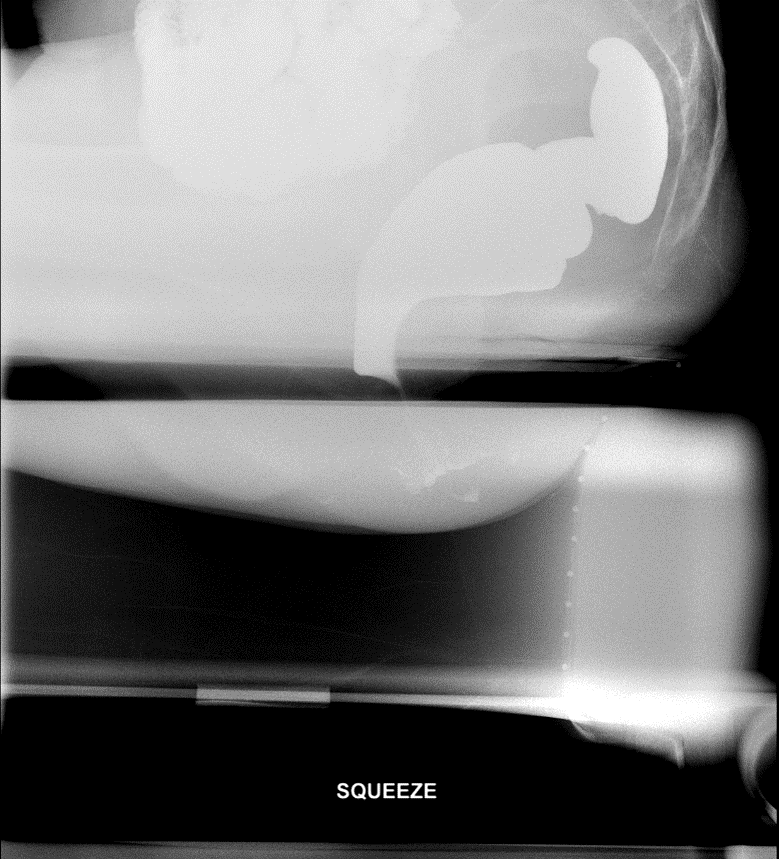

- Obtain spot films while that patient performs the following maneuvers:

- Squeeze

(key image 3).

- This should be done with maximum voluntary contraction of the sphincter and pelvic floor muscles.

- Ask the patient to try and use their muscles as if they were trying to hold in a bowel movement.

- Strain

- Ask the patient to "bear down" or increase their abdominal pressure while trying not to have a bowel movement.

- Once you have obtained images during the “rest,” "squeeze," and "strain" maneuvers, have the patient evacuate the barium.

- Obtain a cine loop of the evacuation